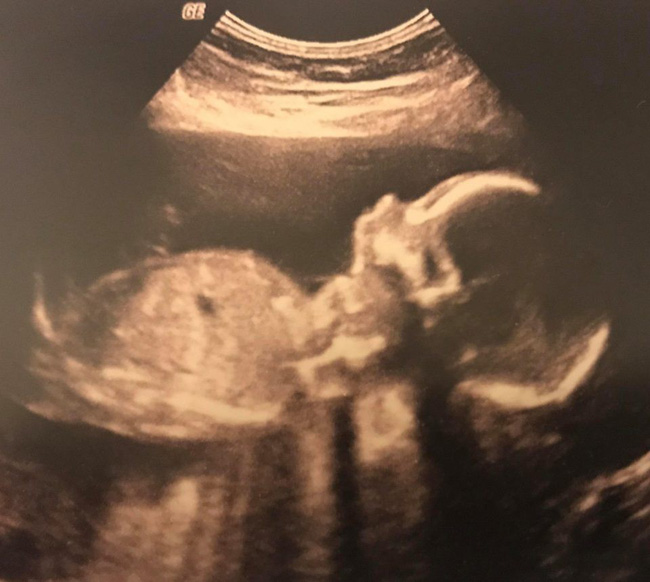

Thai nhi phát triển khỏe mạnh cho tới tuần thứ 25 thì mẹ bất ngờ vỡ ối.

Laura kể rằng khi mang thai đến tuần thứ 20, cô và chồng là anh Steven McCusker đã vô cùng hân hoan khi biết đó là 1 bé trai. Laura đã trải qua một quá trình mang thai khá khó khăn khi cô được chẩn đoán mắc bệnh Rhesus, khiến các kháng thể trong máu của người mẹ phá hủy các tế bào máu của em bé. Tuy nhiên, căn bệnh này có thể được kiểm soát bằng cách tiêm thuốc. Cặp đôi đã cùng nhau chuẩn bị rất nhiều đồ dùng, từ chăn gối, quần áo sơ sinh, xe đẩy và cả gấu bông để chuẩn bị cho sự chào đời của cậu con trai nhỏ. Thế nhưng, khi thai được 25 tuần thì Laura bất ngờ bị vỡ ối. Ngay lập tức, người mẹ được đưa vào bệnh viện Ninewells, Dundee, Scotland cấp cứu.